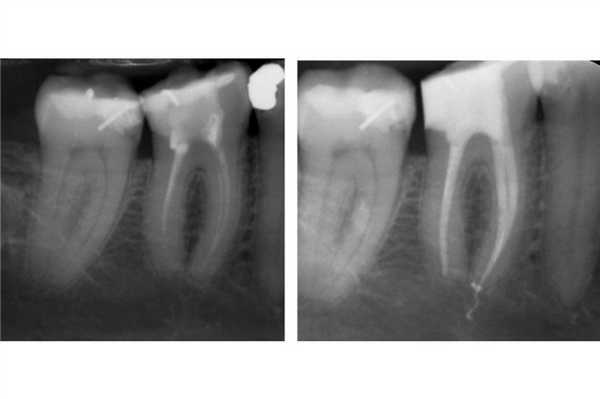

Фото 1. Повторное эндодонтическое лечение и фиксация E.max накладки на зуб LR6 a) Рентгенограмма до ревизии канала. b) Повторное лечение корневого канала и формирование композитной культи. Пациент был направлен к своему лечащему стоматологу для выполнения реставрации с перекрытием бугров. с) Препарирование под накладку; дистальный край сформирован на композитной основе. d) Изоляция коффердама перед фиксацией. e) Изолирование соседних зубов при помощи тефлоновой ленты. f) Фиксация накладки на композитный цемент. g) Очистка излишков цемента. h) Вид после фиксации.

DME менее важен при использовании традиционных цементов (цинк-фосфатных или СИЦ) для фиксации непрямых реставраций. Данные материалы мене чувствительные к промахам изоляции, а их излишки могут быть удалены после полной полимеризации. Однако в подобных случаях достаточно сложно получить качественный оттиск (фото 2).

Фото 2. Лечение корневых каналов и формирование композитной культи на зубе LL6. Пациент был направлен к лечащему врачу для изготовления накладки с перекрытием бугров. Золотая накладка была зацементирована на Fuji Plus. Дистальный край находился под десной, а край накладки был сформирован на композитной реставрации (DME). Граница препарирования на всех поверхностях находилась в границах тканей зуба, кроме дистальной поверхности. Рентгенограмма, полученная через год, демонстрирует признаки заживления периапикального поражения.